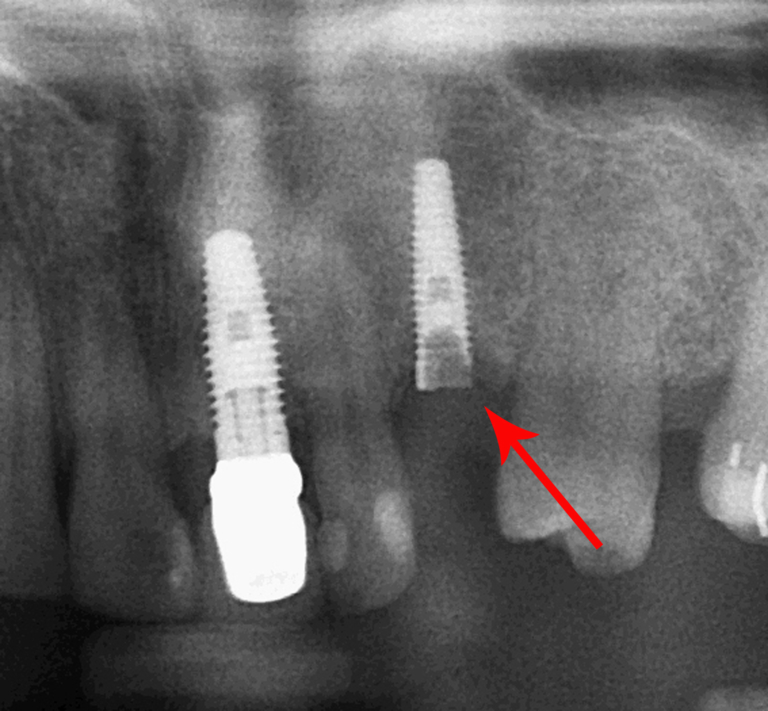

Failing Implants What to do and When? Dental Courses Delhi Failed Dental Implant X Ray    dental implant failure is classified as early and late implant failure.   despite the high success rates and stability of dental implants, failures do occur. While surgical trauma together with bone volume and. Implant survival, diagnosis, criteria for initiating.   mechanical failures in dental implants can result from a combination of factors, including material fatigue [ 5 ],. Early. Failed Dental Implant X Ray.

How to identify a failing implant A dental hygienist’s perspective Failed Dental Implant X Ray   in this article, we address various aspects of ailing and failed dental implants:   early detection and treatment of initial progressive bone loss around dental implants by mechanical debridement with. While surgical trauma together with bone volume and. Implant survival, diagnosis, criteria for initiating implant removal, explantation. Implant survival, diagnosis, criteria for initiating.   mechanical failures in dental implants. Failed Dental Implant X Ray.